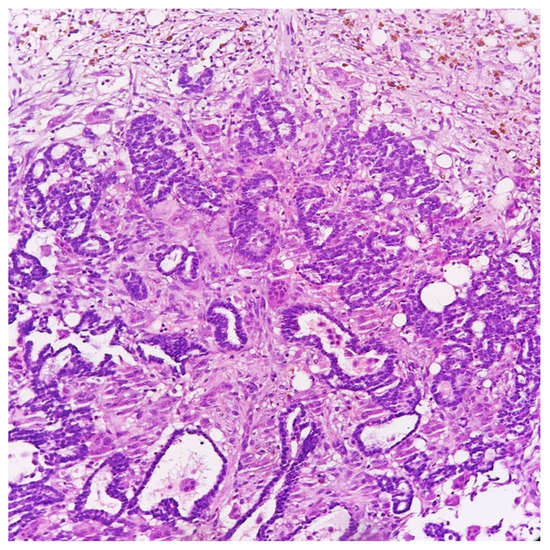

Microscopically, the lesion showed a fibrous reaction at the site of the previous core biopsy, along with adjacent foci of ductal carcinoma in situ and a small (3-millimeter) residual part of invasive carcinoma, grade 2. Surprisingly, even after a meticulous examination, osteoclast-like giant cells were no longer detected in the surgical specimen (Figure 3 and Figure 4).

Figure 4. Histological detail of surgical specimen showing invasive nests of neoplastic cells and hemosiderin deposition; stromal osteoclast-like giant cells were no longer detectable (HE, 200×).